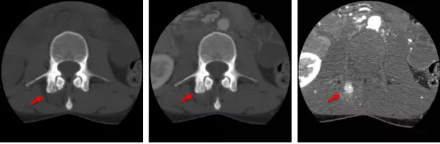

骨智能柔性減影成像功能發(fā)現(xiàn)隱匿骨占位病灶